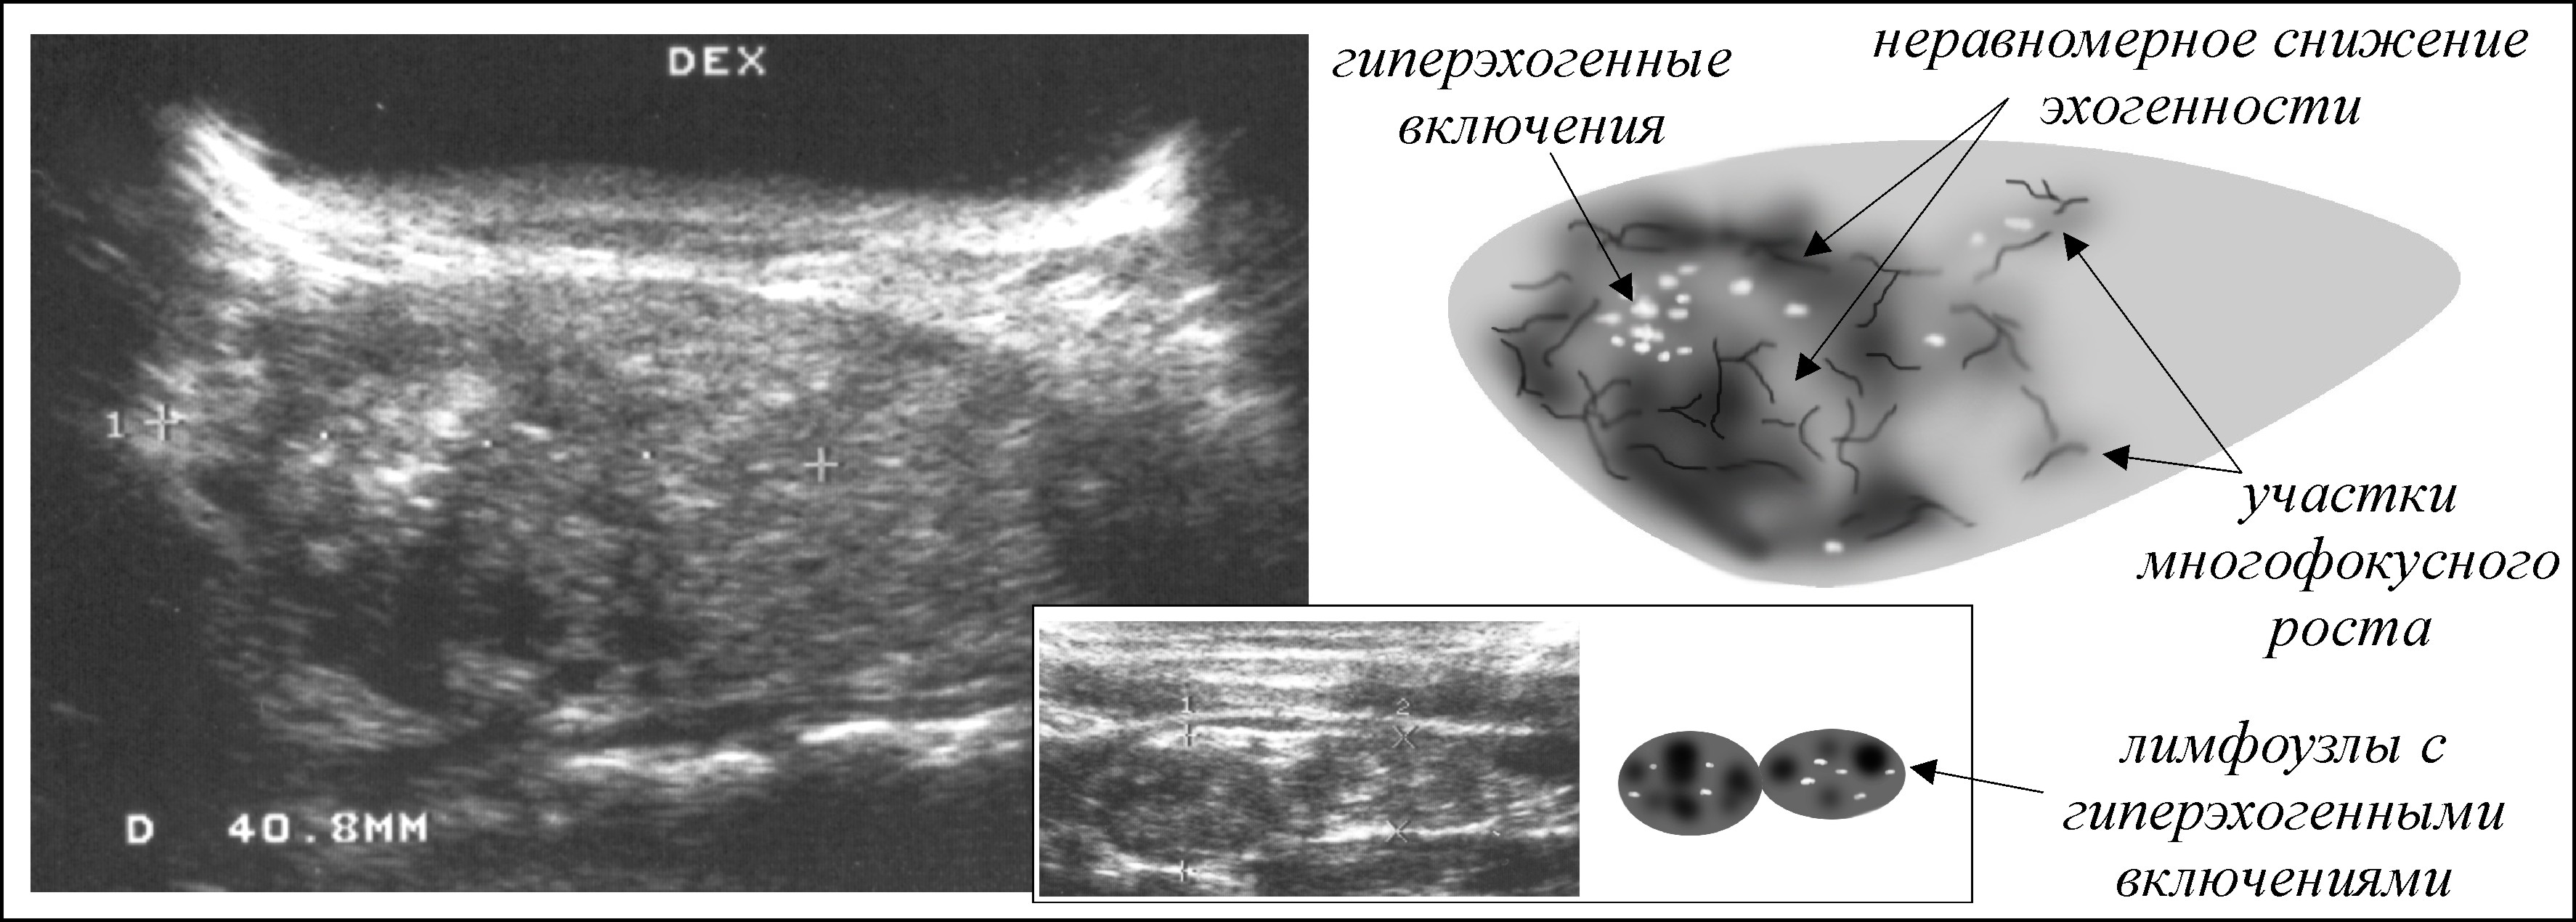

Метастатические поражения печени в ультразвуковом изображении характеризуются